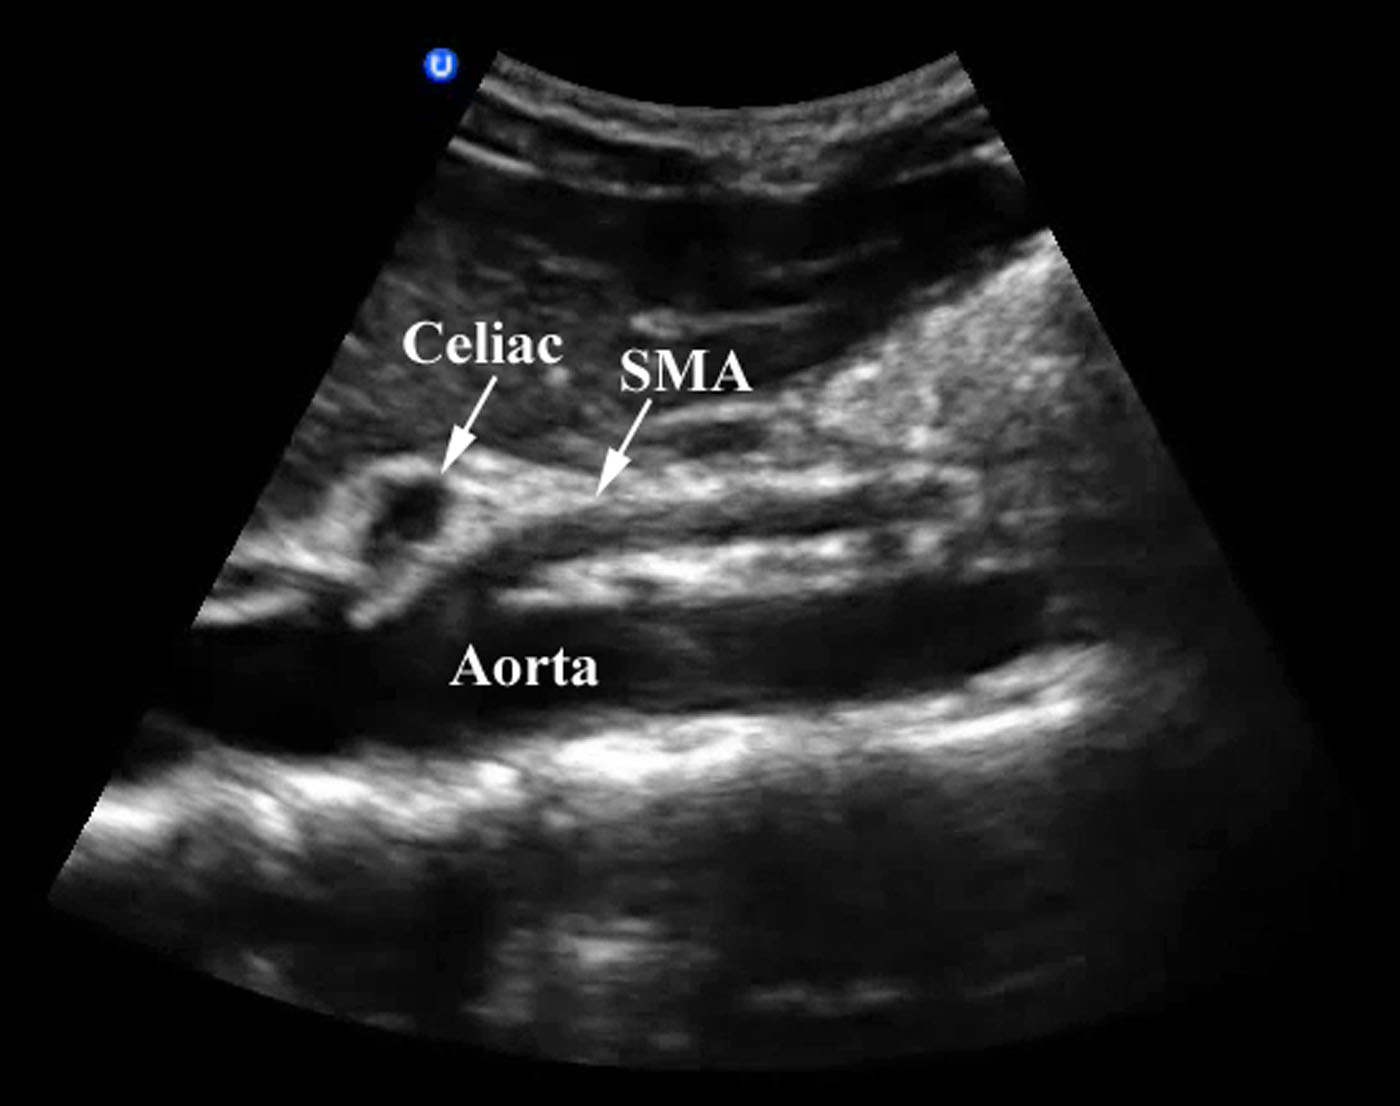

- About 1 cm inferior to the celiac trunk arises the superior mesenteric artery (SMA). Renal arteries arise on either side 1cm below SMA. Although these cannot be seen on a sagittal view of the aorta, they can sometimes be identified with careful transverse scanning.

- In long axis the SMA can be found running parallel to the aorta.

- Figure 2. Aorta imaged in long axis with the celiac trunk and SMA branches